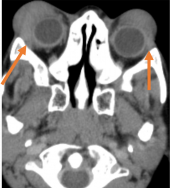

USG Doppler – shows increased velocity with reversal of blood flow direction, dilated Superior Ophthalmic Vein (SOV) and arterial pulsations.

CT/MRI - proptosis, EOM enlargement, dilated and tortuous SOV, with engorgement and early enhancement of the ipsilateral cavernous sinus. CT Angiography- differentiate direct and indirect CCF but cerebral angiography is used for accurate diagnosis and intervention. |

Traumatic carotid-cavernous fistula) Axial T2WI MRI of right orbit showing dilated superior ophthalmic vein along its whole course (orange arrow) b) Coronal T2WI MRI showing dilated superior ophthalmic vein (white dotted arrow) with engorgement of the extra ocular muscles compared to the contralateral normal side (orange arrows) |